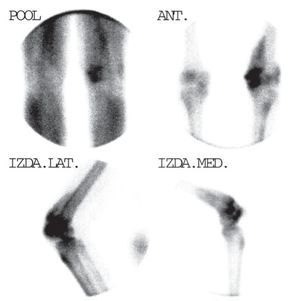

Además, podemos encontrar hipercaptaciones focales a diversos niveles, tanto óseas como extraóseas, que variarán en función de la patología concreta del paciente (figs. 1 y 2).

Fig. 2. Gammagrafía ósea con MDP-99mTc sobre miembros inferiores donde se aprecia calcificación extraósea sobre muslo izquierdo, hallazgo frecuente en las enfermedades metabólicas óseas.